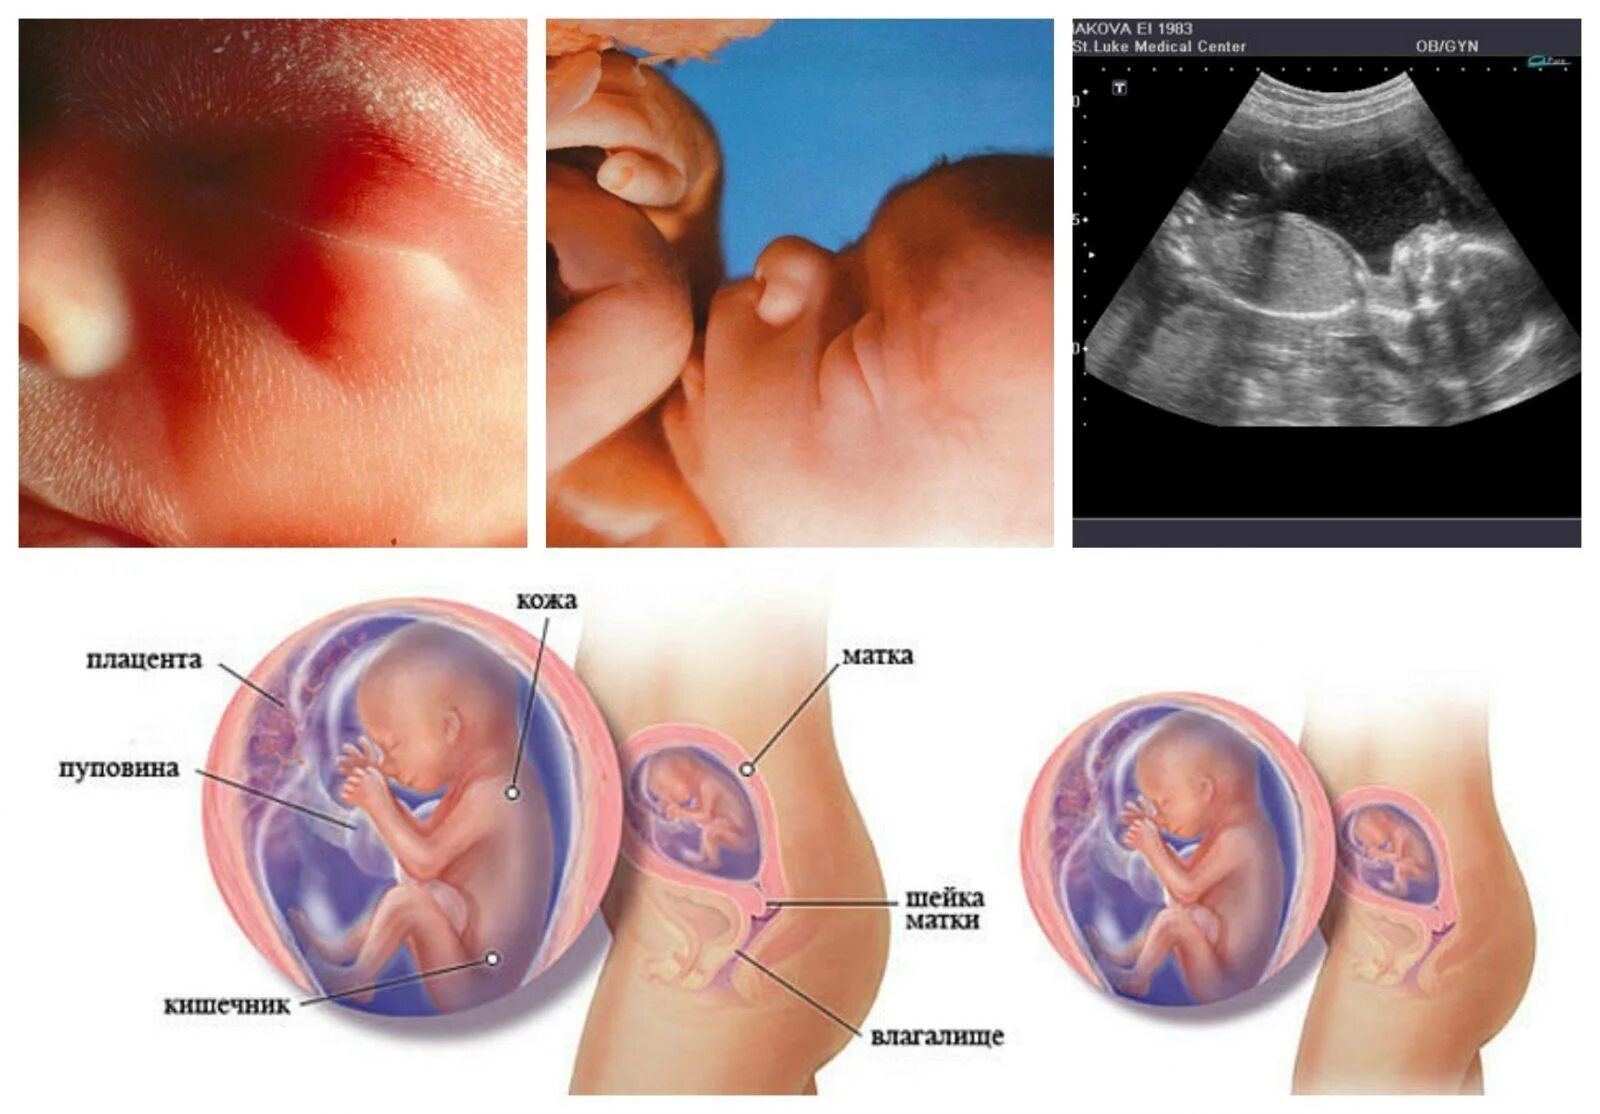

20 недель беременности ощущение